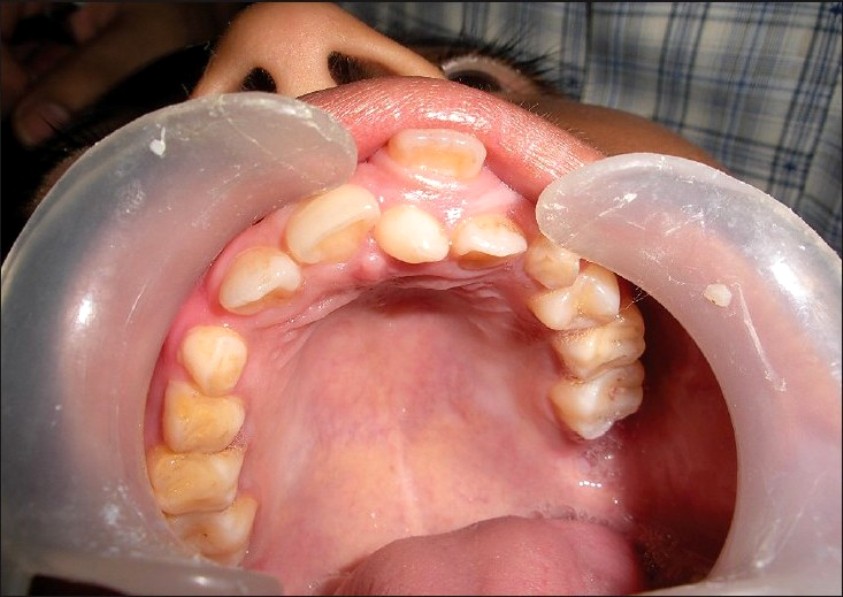

EXTREME CASES

Hyperdontia is the condition of having supernumerary teeth, or teeth that appear in addition to the regular number of teeth. They can appear in any area of the dental arch and can affect any dental organ.

There is evidence of hereditary factors along with some evidence of environmental factors leading to this condition. While a single excess tooth is relatively common, multiple hyperdontia is rare in people with no other associated diseases or syndromes. Many supernumerary teeth never erupt, but they may delay eruption of nearby teeth or cause other dental or orthodontic problems. Molar-type extra teeth are the rarest form. Dental x-rays are often used to diagnose hyperdontia.

When classified by position, a supernumerary tooth may be referred to as a mesiodens, a paramolar, or a distomolar.

The most common supernumerary tooth is a mesiodens, which is a malformed, peg-like tooth that occurs between the maxillary central incisors.